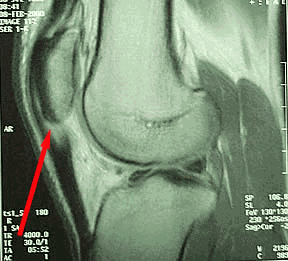

Estudios de imágenes

El diagnóstico de rodilla de saltador es fundamentalmente clínico, por lo que las pruebas de imagen no son necesarias de forma rutinaria, aunque pueden ser útiles para descartar otras patologías.

La radiografía simple puede mostrar signos como una imagen de radiolucencia o un alargamiento del polo inferior de la rótula, pero su valor diagnóstico es limitado.

La ecografía musculoesquelética puede evidenciar engrosamiento e hipoecogenicidad de las fibras del tendón, y mediante ecodoppler con color, se pueden detectar signos de hipervascularidad o neovascularización peritendinosa.

La resonancia magnética (RM) y la ecografía son muy sensibles para detectar alteraciones tendinosas tanto en pacientes con síntomas como en asintomáticos. Esto genera un alto número de falsos positivos, lo que limita su utilidad en pruebas de rutina.

La disponibilidad de unidades de ecografía portátiles y más económicas ha favorecido su uso en el entorno clínico. Además, algunos autores han propuesto tratamientos como la esclerosis dirigida a la neovascularización, guiada por ecodoppler, como una opción terapéutica en casos seleccionados.